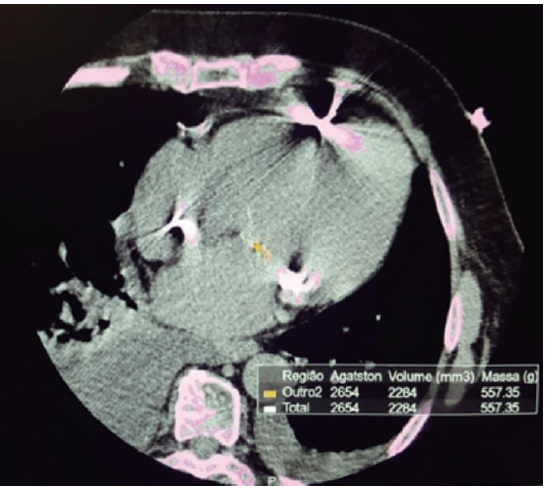

Homem de 81 anos, hipertenso, dislipidêmico, diabético, com histórico de angioplastia da artéria descendente anterior com stent farmacológico há 5 anos, comparece ao consultório do cardiologista com queixa de dispneia progressiva nos últimos 4 meses, atualmente aos moderados esforços. Faz uso de anlodipino 5 mg + perindopril 5 mg, 1x ao dia. Nega angina, palpitações ou síncope. Ao exame: RCR, 2T, sopro sistólico de ejeção em foco aórtico 2+/6+, FC 80 bpm, PA 136x68 mmHg. Pulsos simétricos, com amplitude normal. Ausculta pulmonar sem alterações. Eletrocardiograma com sobrecarga atrial e ventricular esquerda. Foi solicitado ecocardiograma, que evidenciou área valvar aórtica de 0.8 cm2 e área valvar indexada de 0,58 cm²/m², gradiente médio de 33 mmHg, função sistólica preservada (FE 71%), disfunção diastólica, hipertrofia ventricular esquerda e volume ejetado indexado de 32 mL/m². Realizou o escore de cálcio da valva aórtica mostrado abaixo.

Nesse caso, a tomografia de cálcio valvar indica a presença de estenose aórtica importante, baixo fluxo e